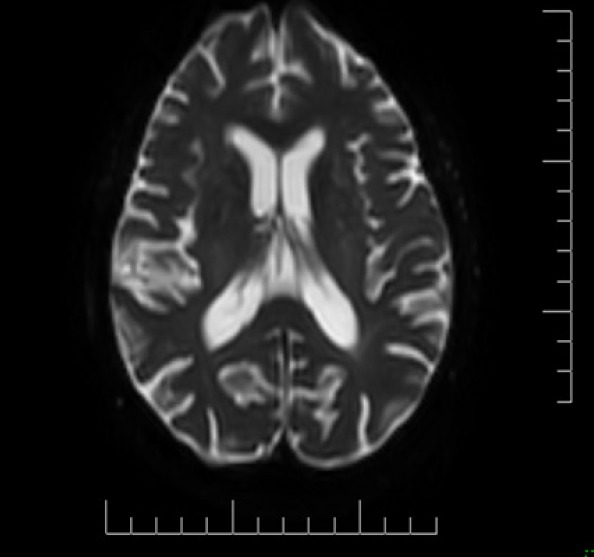

Alzheimer disease (AD) is the most common cause of dementia worldwide. Its clinical manifestations include a progressive loss of memory and other cognitive domains, as well as brain atrophy. An elevated homocysteine level (>15 µmol/L), known as hyperhomocysteinemia, is also an attributing risk factor for AD, vascular pathologies, and brain atrophy. Neuroimaging studies including T2-weighted magnetic resonance imaging scans revealed white matter hyperintensities in the periventricular and deep white matter, enlarged ventricles, widened sulci, and decreased white matter mass, which are features of aging, as well as cerebrovascular changes. This case series investigated changes in biochemical marker levels including serum homocysteine, folate, and vitamin B12, and the degree of atrophic variations in cortical-subcortical white matter in AD. The present study hypothesized that serum homocysteine levels might be used as a surrogate marker to screen for AD at an earlier stage.

Abstract Image

阿尔茨海默病(AD)是全球最常见的痴呆症病因。其临床表现包括记忆力和其他认知能力的逐渐丧失,以及脑萎缩。同型半胱氨酸水平升高(>15 µmol/L),即高同型半胱氨酸血症,也是导致老年痴呆症、血管病变和脑萎缩的一个危险因素。包括 T2 加权磁共振成像(MRI)扫描在内的神经影像学研究显示,脑室周围和深部白质中存在白质高密度(WMH),脑室扩大,脑沟增宽,白质质量减少,这些都是衰老以及脑血管变化的特征。本系列病例研究了 AD 患者血清同型半胱氨酸、叶酸和维生素 B12 等生化标志物水平的变化,以及皮质-皮质下白质萎缩变异的程度。本研究假设,大脑中的血清同型半胱氨酸水平可作为一种替代标志物,用于早期筛查 AD。